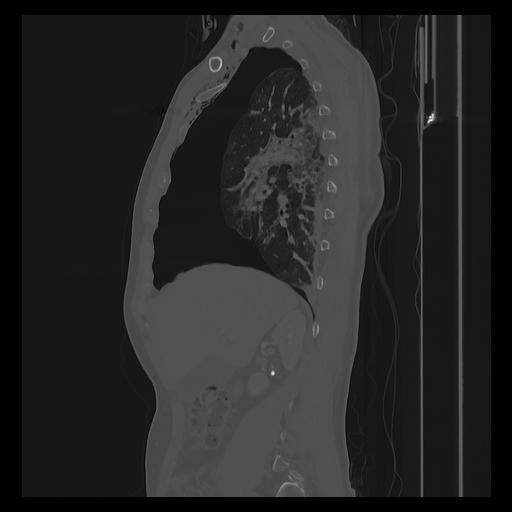

33 PULMON,CE,Sagittal,3.000,PULMON,Sagittal,